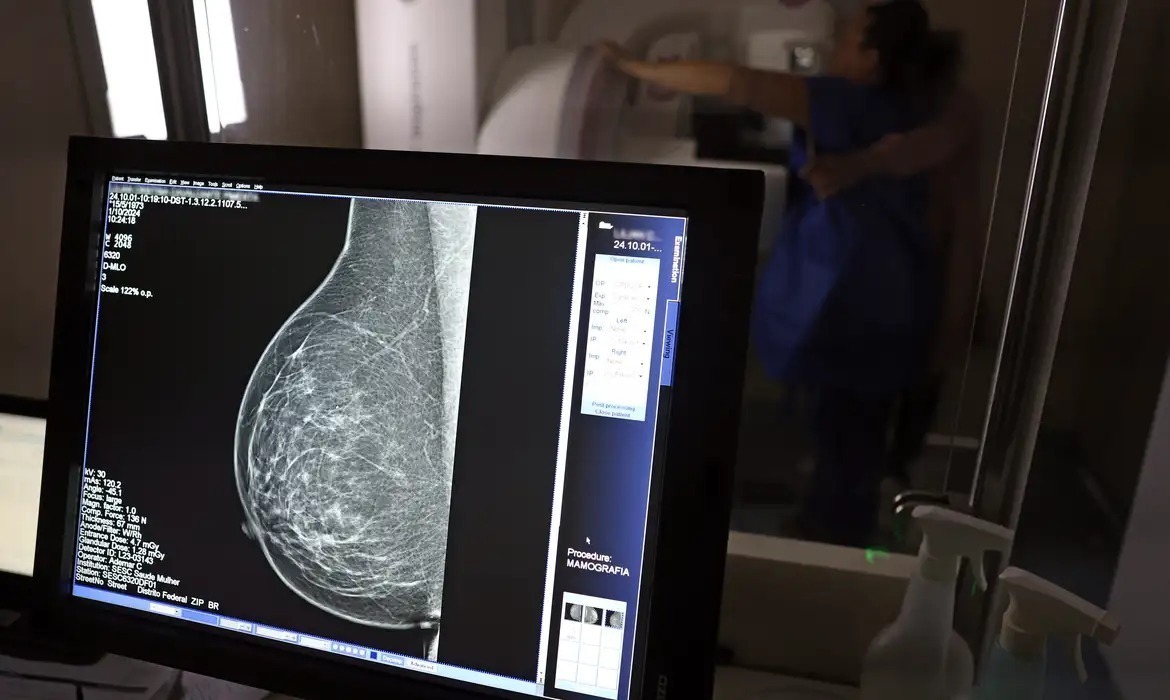

Uma mulher presa em Mato Grosso do Sul conseguiu na Justiça o direito de realizar exames médicos após apresentar suspeita de câncer de mama. A decisão foi obtida com apoio da Defensoria Pública.

A mulher foi presa recentemente para começar a cumprir pena de 11 anos, 6 meses e 3 dias em regime fechado, sendo levada para a Penitenciária de Jateí. Durante a audiência de custódia, ela revelou que já tinha exames agendados para investigar um possível câncer de mama.